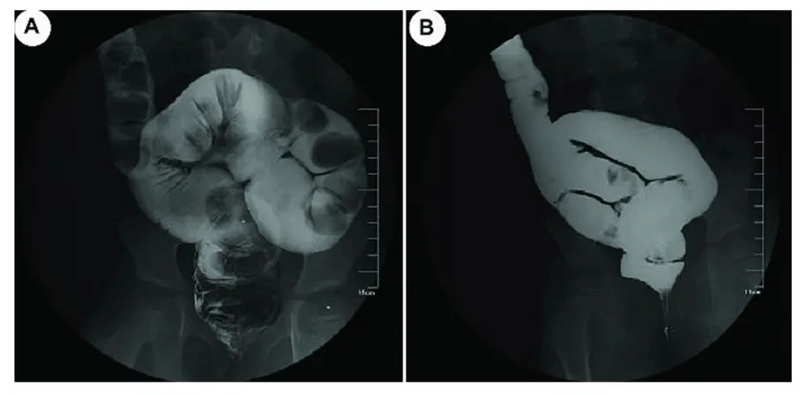

FMT改善了患者粪便嵌塞[22]